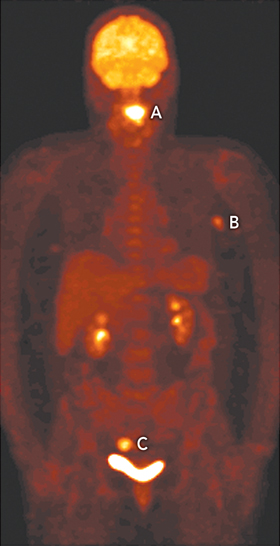

A 65-year-old woman underwent integrated fluorodeoxyglucose positron emission tomography and computed tomography (FDG-PET/CT [Philips GXL, Philips Medical Systems, Milpitas, Calif, USA]) to stage a newly diagnosed squamous cell carcinoma of the tongue (Figure, A). The scan revealed two additional, unexpected synchronous tumours, one in the left axilla (B) and the other in the sigmoid colon (C). The patient underwent subtotal glossectomy, after which further investigations confirmed a node-positive neuroendocrine carcinoma of the left breast and a dysplastic colonic tubulovillous adenoma. The detection of three synchronous tumours of different aetiology in the one patient on PET is rare. Previous cases of synchronous tumours detected on PET involved tumours of the head and neck, upper gastrointestinal tract and lungs, thought to be related to shared risk factors, such as smoking.1